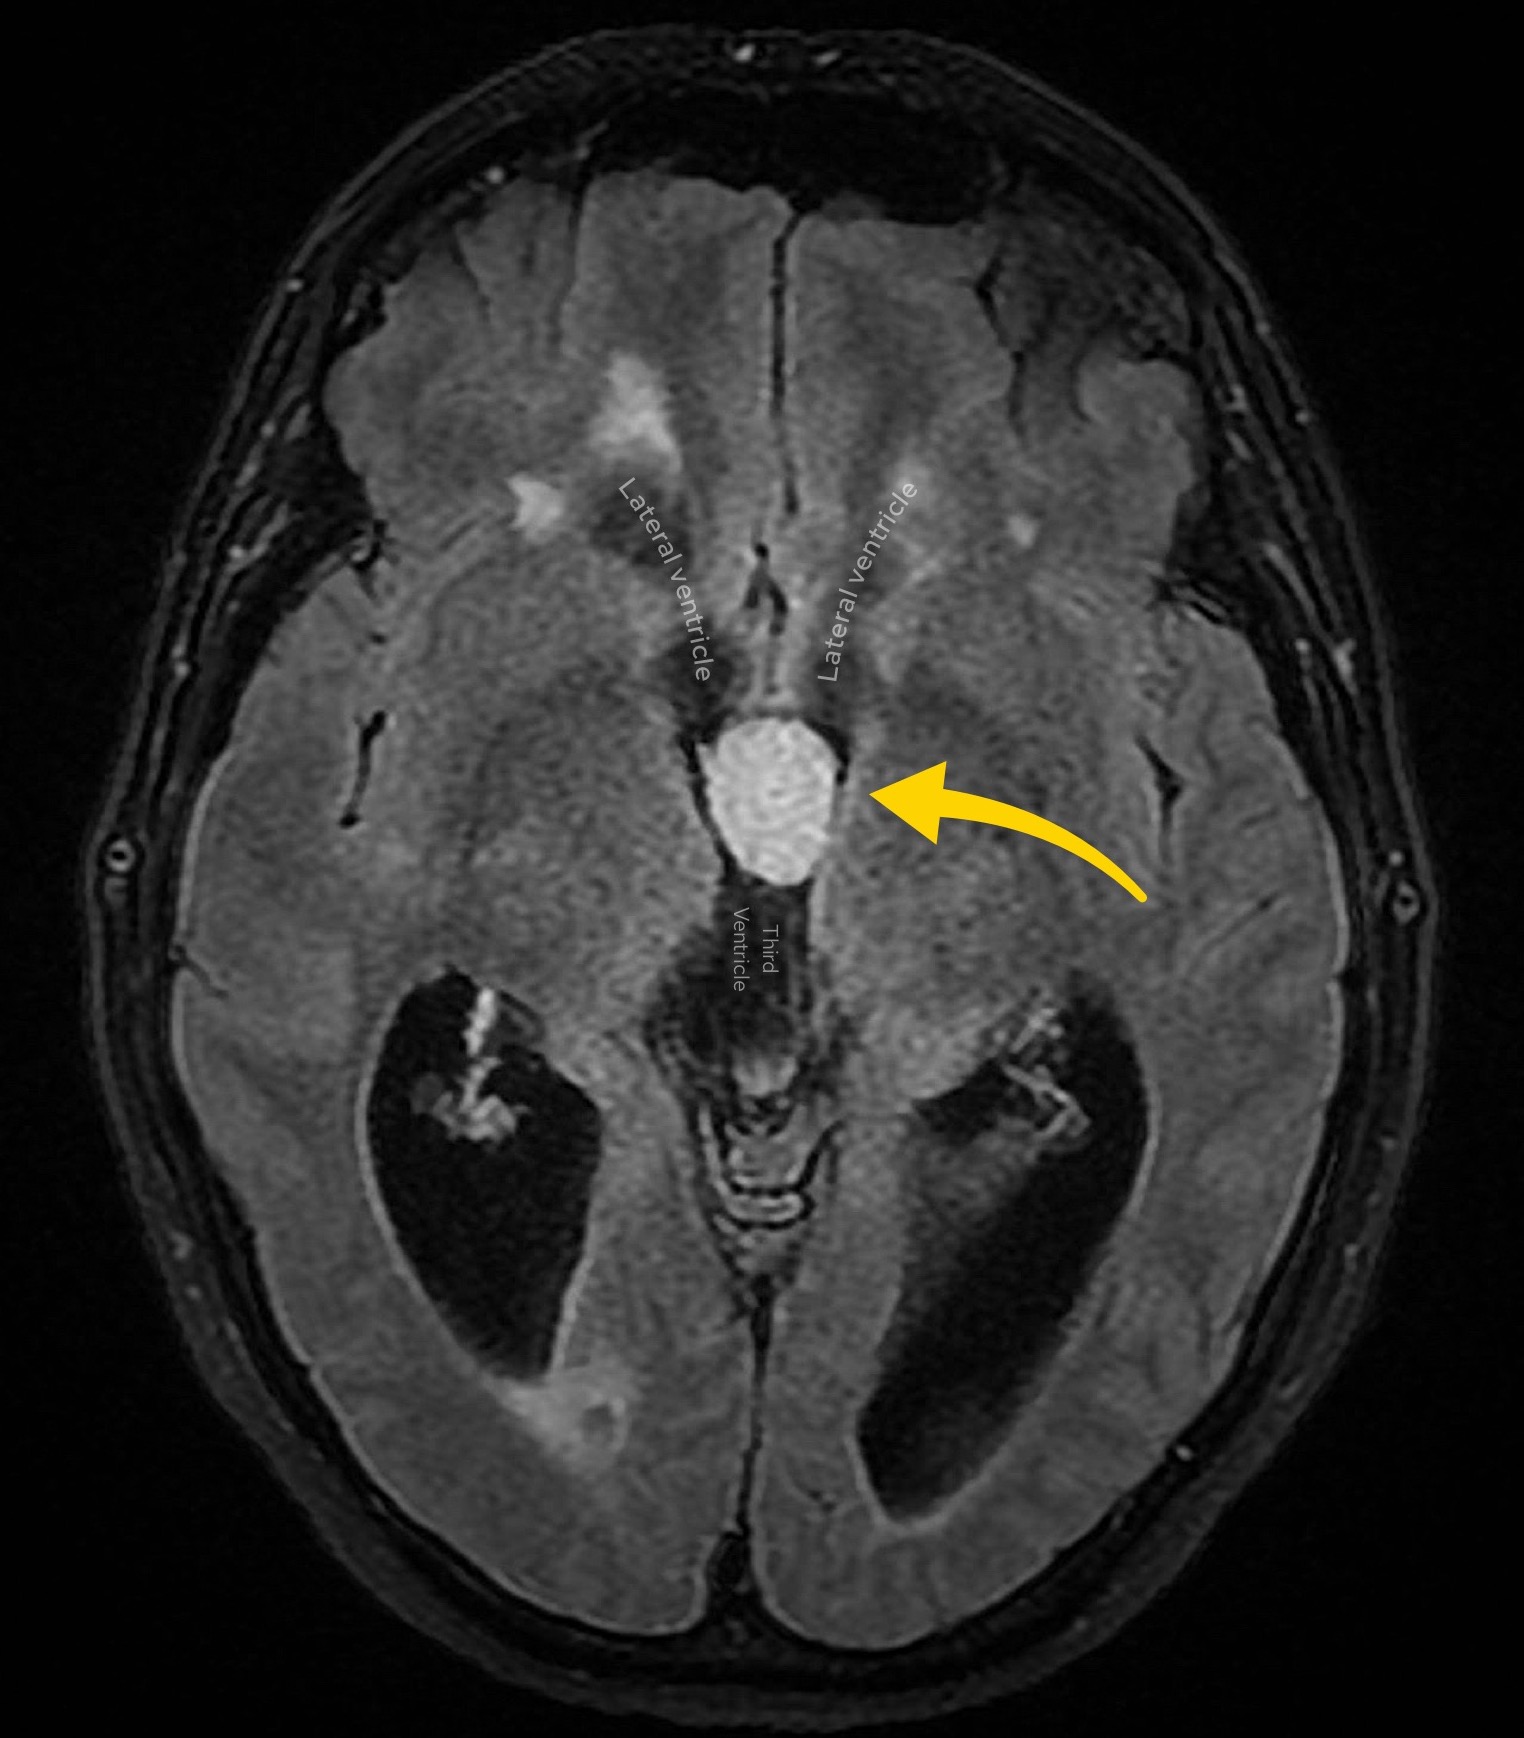

Case 5

A female in her 50s presents with gait disturbance. Here are two images from a MRI head (FLAIR sequence). What is the most likely diagnosis?

Choose from one of the following options: